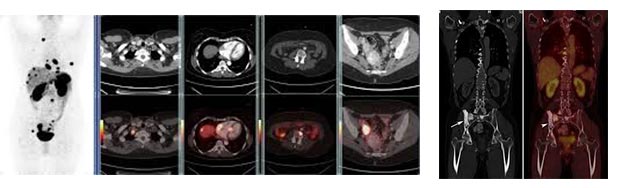

Позитронно емісійна томографія (ПЕТ) є винятково ефективним методом клінічних досліджень пацієнтів з онкопатологією; його широке поширення в останнє десятиліття пов’язане насамперед з розробкою і технічним удосконаленням приладів, призначених для дослідження всього тіла. Сучасна радіоізотопна діагностика дає дуже високі результати візуалізації ПЕТ дозволяє одержувати унікальну інформацію про метаболічну активність пухлин і зміни метаболізму, пов’язаних із проведеною терапією.За швидкістю та інтенсивностю нагромадження ізотопопомічених метаболітів або спеціальних лікарських препаратів можна судити про біологічні особливості пухлинної тканини в порівнянні з тканиною інтактною, а також – що особливо цінне для онкології – оцінювати ефективність лікування і складати прогноз подальшого перебігу процесу. При даному дослідженні сканується все тіло пацієнта. Обстеження ПЕТ КТ незамінне при діагностиці та перевірці відповіді на отримане пацієнтом лікування. PET- СТ- моллекулярная томографія. Відділення ядерної медицини працює на новітньому у світі медицини апараті Siemens PET-СТ. Молекулярний СТ в комбінації з технологіями TOF і HD.Прі діагностиці раку, плануванні лікування та визначенні його ефективності, дуже важливо не тільки отримати якісне і точне зображення, а й правильна і точна його трактування.

Позитронно емісійна томографія (ПЕТ) є винятково ефективним методом клінічних досліджень пацієнтів з онкопатологією; його широке поширення в останнє десятиліття пов’язане насамперед з розробкою і технічним удосконаленням приладів, призначених для дослідження всього тіла. Сучасна радіоізотопна діагностика дає дуже високі результати візуалізації ПЕТ дозволяє одержувати унікальну інформацію про метаболічну активність пухлин і зміни метаболізму, пов’язаних із проведеною терапією.За швидкістю та інтенсивностю нагромадження ізотопопомічених метаболітів або спеціальних лікарських препаратів можна судити про біологічні особливості пухлинної тканини в порівнянні з тканиною інтактною, а також – що особливо цінне для онкології – оцінювати ефективність лікування і складати прогноз подальшого перебігу процесу. При даному дослідженні сканується все тіло пацієнта. Обстеження ПЕТ КТ незамінне при діагностиці та перевірці відповіді на отримане пацієнтом лікування. PET- СТ- моллекулярная томографія. Відділення ядерної медицини працює на новітньому у світі медицини апараті Siemens PET-СТ. Молекулярний СТ в комбінації з технологіями TOF і HD.Прі діагностиці раку, плануванні лікування та визначенні його ефективності, дуже важливо не тільки отримати якісне і точне зображення, а й правильна і точна його трактування.

Радіоізотопна діагностика. В онкологічній практиці застосовується метод сканування органів при підозрі їх на пухлинне ураження (первинне або метастатичне). Метод контактної бета-радіометрії використовується в діагностиці меланом шкіри, при поверхнево розташованих пухлинах молочної залози, при хворобі Педжета.

Радіонуклідні методи. Радіонуклідні методи дуже перспективні (мається на увазі створення опухолеспеціфіческіх мічених антитіл). В даний час для діагностики застосовують сцинтиграфію кістяка, мозку, легенів; для характеристики функціонального стану – сцинтиграфію нирок, печінки.

Радіоімунологічне дослідження засноване на аналізі вмісту моноклональних антитіл у досліджуваних тканинах, дозволяє виявляти багато видів пухлин на ранніх етапах розвитку процесу, коли розміри пухлин малі. Тести на виявлення антитіл, специфічних для певного виду пухлин, дозволяють найбільш ефективно вирішувати проблему низької деталізації по контрасту між тканинами схлжої щільності, характерної для звичайних рентген-досліджень.